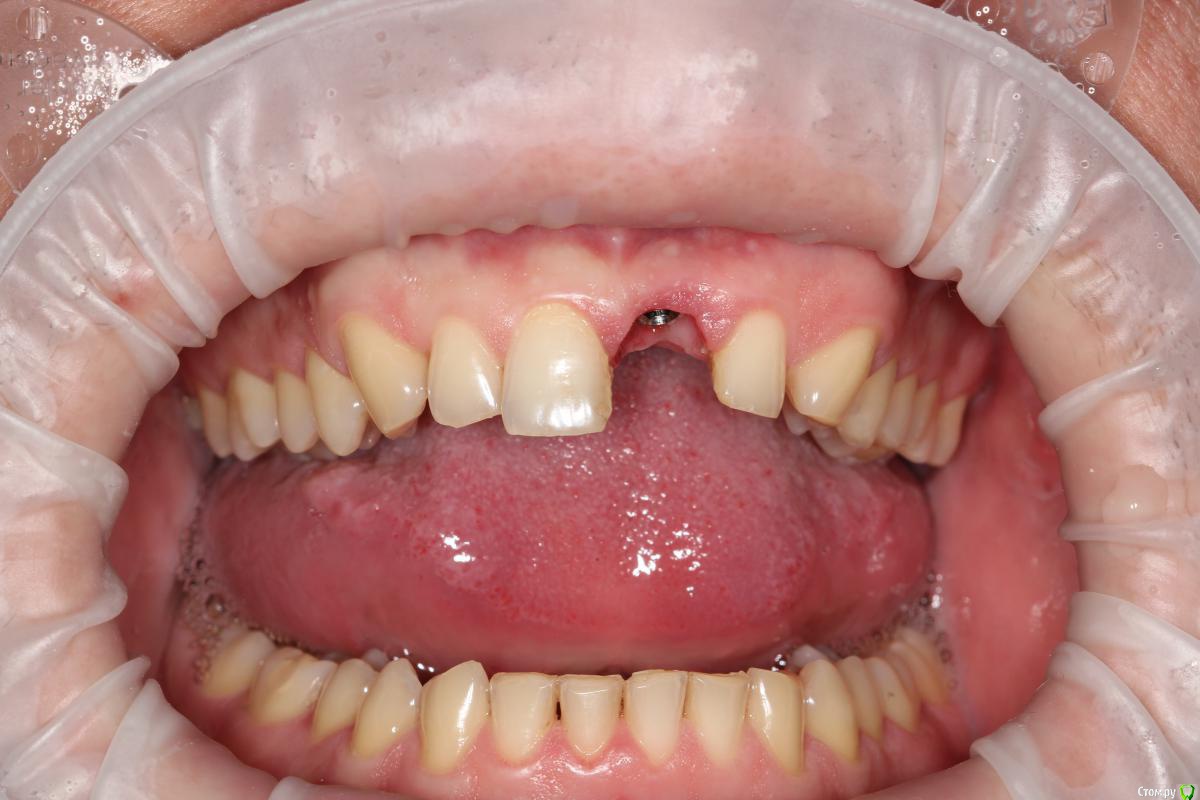

Популярный пост Mane Опубликовано 8 февраля, 2015 Популярный пост Поделиться Опубликовано 8 февраля, 2015 Зафиксировал в субботу. Собственно удалось размоделировать десну просто временной коронкой с заданным профилем прорезывания. Но для этого необходимо было выполнить ряд условий. Каких, доктора? http://i1218.photobucket.com/albums/dd412/Edikn73/emergence%20profile/Emergenceprofile001_zps040f2603.jpg http://i1218.photobucket.com/albums/dd412/Edikn73/emergence%20profile/Emergenceprofile002_zpsaa7acb0b.jpg http://i1218.photobucket.com/albums/dd412/Edikn73/emergence%20profile/Emergenceprofile003_zps259f0885.jpg http://i1218.photobucket.com/albums/dd412/Edikn73/emergence%20profile/Emergenceprofile004_zps6a15b901.jpg http://i1218.photobucket.com/albums/dd412/Edikn73/emergence%20profile/Emergenceprofile005_zps51a41bc2.jpg http://i1218.photobucket.com/albums/dd412/Edikn73/emergence%20profile/Emergenceprofile006_zps3c83a34d.jpg http://i1218.photobucket.com/albums/dd412/Edikn73/emergence%20profile/Emergenceprofile007_zpsba4d3d78.jpg 26 Ссылка на комментарий

SDC Опубликовано 8 февраля, 2015 Поделиться Опубликовано 8 февраля, 2015 (изменено) Собственно удалось размоделировать десну просто временной коронкой с заданным профилем прорезывания. Но для этого необходимо было выполнить ряд условий. Каких, доктора? Снять слепок, черкануть на наряде и позвонить в лабу.)) Все, что ниже - детали. А в следующий раз надо завернуть на переделку вкладку с пятым бугорком смоделированным дистально и фиссуры вестибулярная и лингвильная не должны стремиться друг к другу по кратчайшему пути )) - окклюзионная пропеллером смоделирована.И еще бы фиссуры на 7-м я бы завернул заодно - хорош красить кариес - так нам не продать тотал )))) Надо как на 4-м зубе, не больше Надеюсь, что на пользу P.S. И для протокола прицельный в стандартной проекции Изменено 8 февраля, 2015 пользователем SDC Ссылка на комментарий

Mane Опубликовано 10 февраля, 2015 Автор Поделиться Опубликовано 10 февраля, 2015 По поводу профиля прорезывание интересен Ваш протокол. Менялся ли ФДМ на более широкий, делались ли насечки на десне во время фиксации времяхи? Во первых - это заглубление платформы импланта - от будущего зенита до платформы - 3,5 мм . если этого не сделать - ничего не полуитсяпосле тонкого фдм зафиксировал временную коронку с небольшим надрезом по контактам. отдыхала с времянкой 1,5 мес.далее вы видели 1 Ссылка на комментарий

Евгений Ходыкин Опубликовано 20 февраля, 2015 Поделиться Опубликовано 20 февраля, 2015 Врачи, ответьте, плиз, на вопоосы выше. Какие д.б.исходники, кроме 3.5 мм?3.5 мм, как уже было сказано, это идеальное расстояние от зенита будущей реставрации до платформы имплантата. Но, как показывает практика, это, к сожалению, не всегда достижимо. Поэтому лучше всё-таки делать десневую аугментацию для максимального нивелирования возможных расхождений. имхо... 2 Ссылка на комментарий